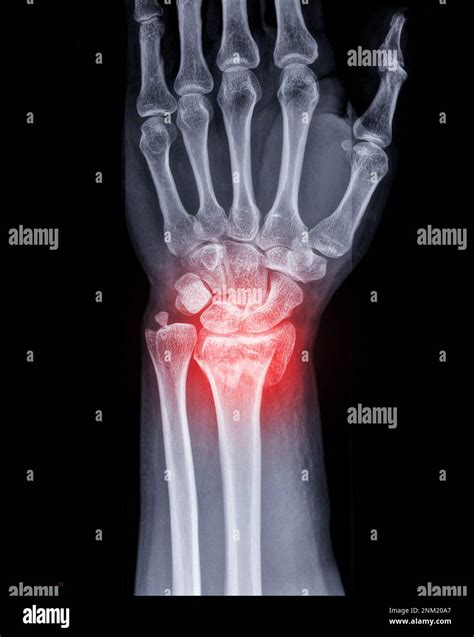

An MRI wrist joint scan is a non-invasive imaging technique that uses magnetic fields and radio waves to produce detailed images of the wrist. Unlike X-rays, which primarily show bones, MRI scans can visualize soft tissues such as ligaments, tendons, and cartilage. This makes MRI particularly useful for diagnosing conditions that affect these structures, such as fractures, ligament tears, and arthritis.

• Fractures: MRI can detect fractures that may not be visible on X-rays, especially in the early stages.

• X-Rays: Useful for detecting bone fractures and certain types of arthritis.

• CT Scans: Provide detailed images of bones and can be useful for detecting fractures and bone abnormalities.